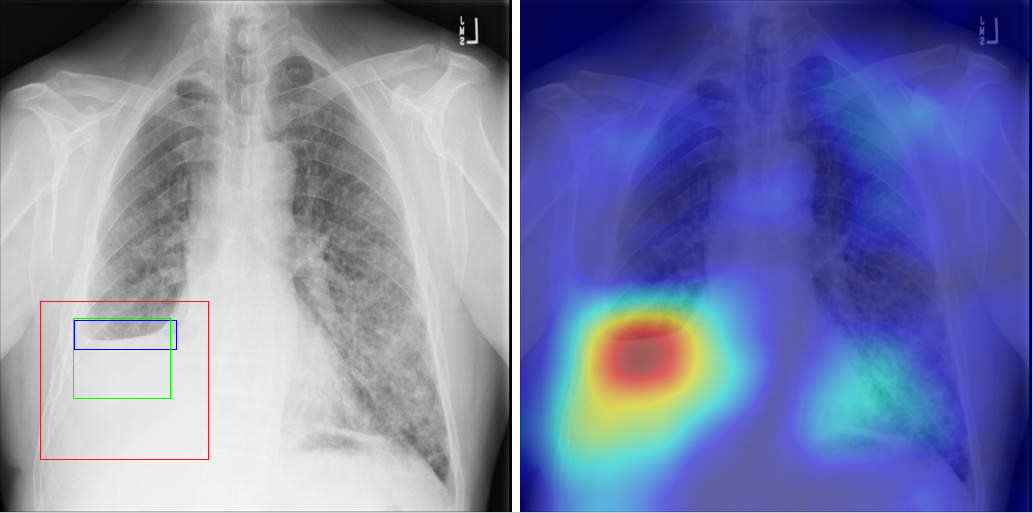

Table 8 to Table 15 illustrate localization results from each of 8 disease classes together with associated report and mined disease keywords. The heatmaps overlay on the original images are shown on the right. Correct bounding boxes (in green), false positives (in red) and the groundtruth (in blue) are plotted over the original image on the left.

In order to quantitatively demonstrate how informative those heatmaps are, a simple two-level thresholding based bounding box generator is adopted here to catch the peaks in the heatmap and later generated bounding boxes can be evaluated against the ground truth. Each heatmap will approximately results in 1-3 bounding boxes. We believe the localization accuracy and AFP (shown in Table 7) could be further optimized by adopting a more sophisticated bounding box generation method, e.g. selective search [47] or Edgebox [18]. Nevertheless, we reserve the effort to do so, since our main goal is not to compute the exact spatial location of disease patterns but just to obtain some instructive location information for future applications, e.g. automated radiological report generation. Take the case shown in Table 8 for an example. The peak at the lower part of the left lung region indicates the presence of “atelectasis”, which confer the statement of “…stable abnormal study including left basilar infilrate/atelectasis, …” presented in the impression section of the associated radiological report. By combining with other information, e.g. a lung region mask, the heatmap itself is already more informative than just the presence indication of certain disease in an image as introduced in the previous works, e.g. [42].

Radiology report Keyword Localization Result

findings include: 1. left basilar atelectasis/consolidation. 2. prominent hilum (mediastinal adenopathy). 3. left pic catheter (tip in atriocaval junction). 4. stable, normal appearing cardiomediastinal silhouette. impression: small right pleural effusion otherwise stable abnormal study including left basilar infiltrate/atelectasis, prominent hilum, and position of left pic catheter (tip atriocaval junction). Effusion; Infiltration; Atelectasis [Uncaptioned image]

Table 8: A sample of chest x-ray radiology report, mined disease keywords and localization result from the “Atelectasis” Class. Correct bounding box (in green), false positives (in red) and the ground truth (in blue) are plotted over the original image.